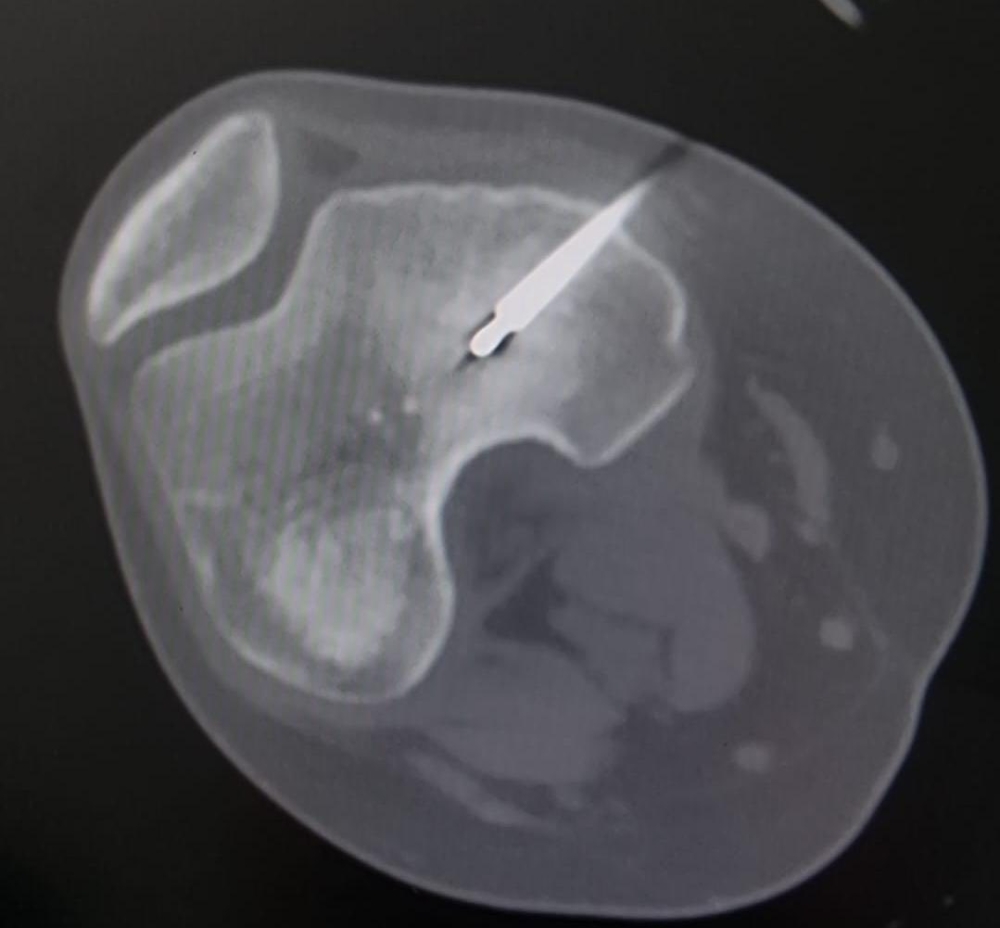

اجرى الكادر الطبي في مستشفى الأميرة بسمة عملية نوعية دقيقة لعلاج ورم عظمي حميد من نوع (Osteoid Osteoma) باستخدام تقنية الكي بالتردد الحراري (Radiofrequency Ablation) الموجهة بالأشعة المقطعية.

وبين الفريق الطبي أن خصوصية هذه الحالة تكمن في عمر المريضة (14 عاماً) حيث استقر الورم مباشرة على صفيحة النمو (Growth Plate) في عظم الفخذ البعيد. وتعتبر هذه المنطقة من الحساسية بمكان إذ ان أي خطأ قد يؤثر على النمو المستقبلي للعظم ما جعل استخدام تقنية الكي الحراري تحديا كبيرا يتطلب دقة فائقة لتجنب إلحاق أي ضرر حراري بالأنسجة المحيطة.